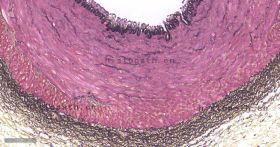

结缔组织狭义上是指其含有的三种纤维:胶原纤维、网状纤维、弹力纤维。结缔组织染色方法亦有很多种,如Masson三色染色法、Van Gieson染色法、Gomori氨银法、Mallory磷钨酸苏木素染色,然而以上染色方法只是侧重于某一两种组织的染色。Russell改良Movat五色套染以其染色丰富、呈色鲜艳而大受欢迎。该染色法常用于显示动脉粥样硬化斑块。苏木素用于染细胞核和弹力纤维,品红用于染细胞质和肌肉纤维,藏红花染胶原组织,阿利新蓝染基质(蛋白聚糖)。

染色结果: